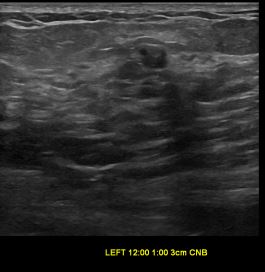

상기환자는 외부검사 이상소견으로 내원하신 60대후반 여성분으로 의심스러운 좌측혹

조직검사 시행해 제자리암으로 진단되었습니다